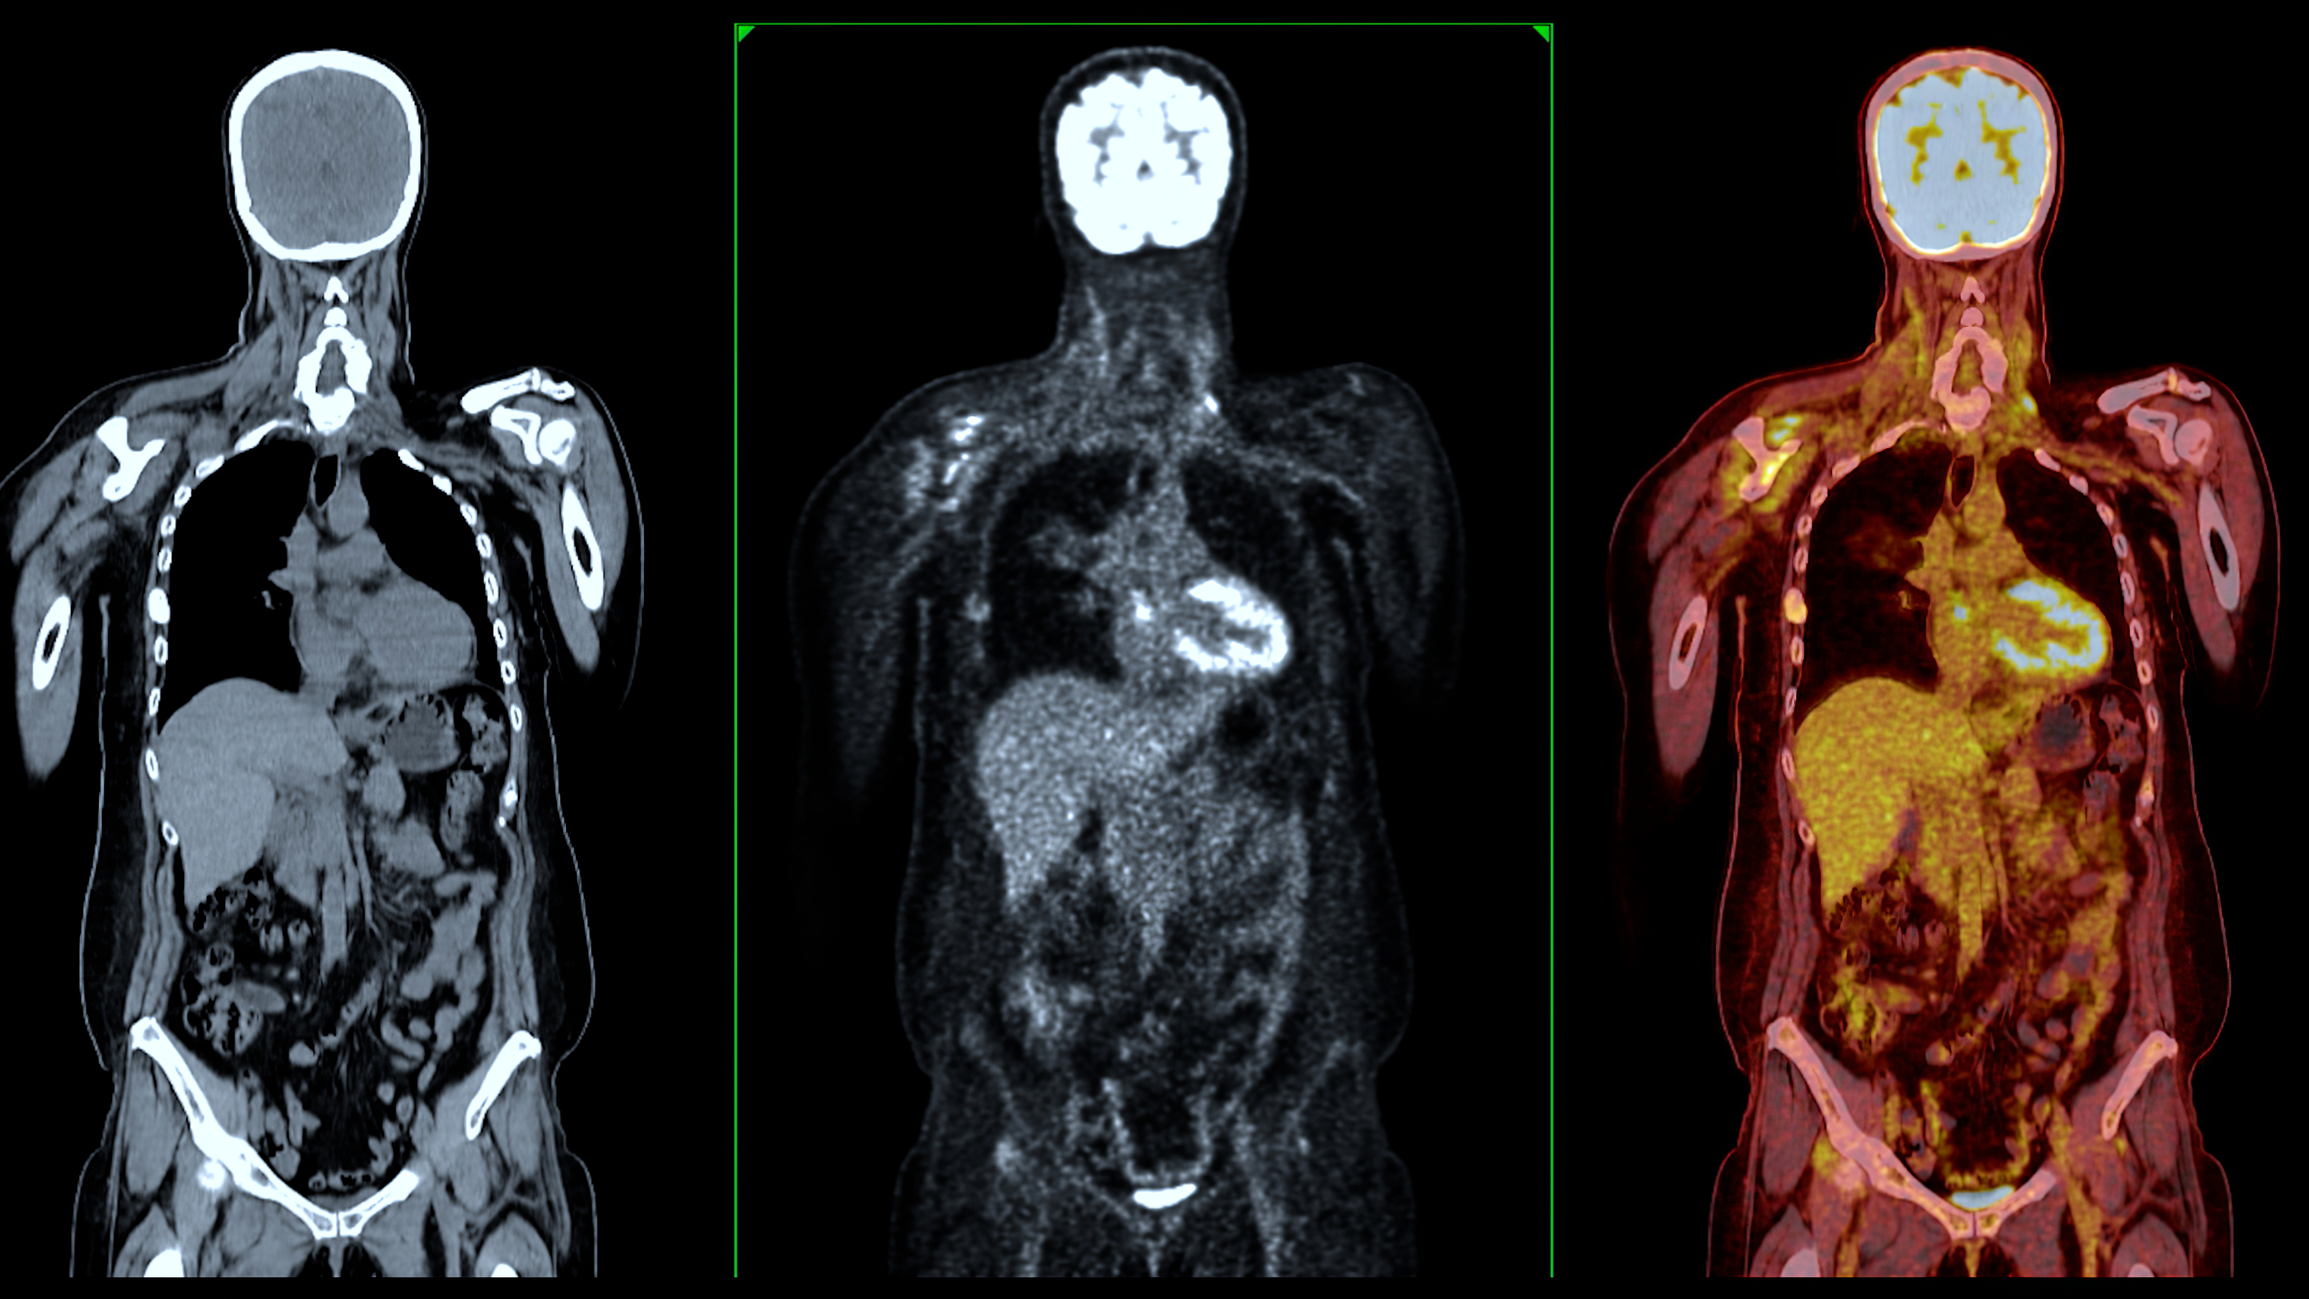

Medical imaging remains central to modern healthcare delivery. From radiography and ultrasound to MRI, PET-CT and hybrid molecular imaging systems, imaging technologies continue to transform diagnosis, treatment planning and disease monitoring.

Nuclear medicine and radiotheranostics are reshaping personalised care. Radiopharmaceutical innovation is accelerating. Quantitative imaging and advanced analytics are redefining how clinicians interpret complex disease.